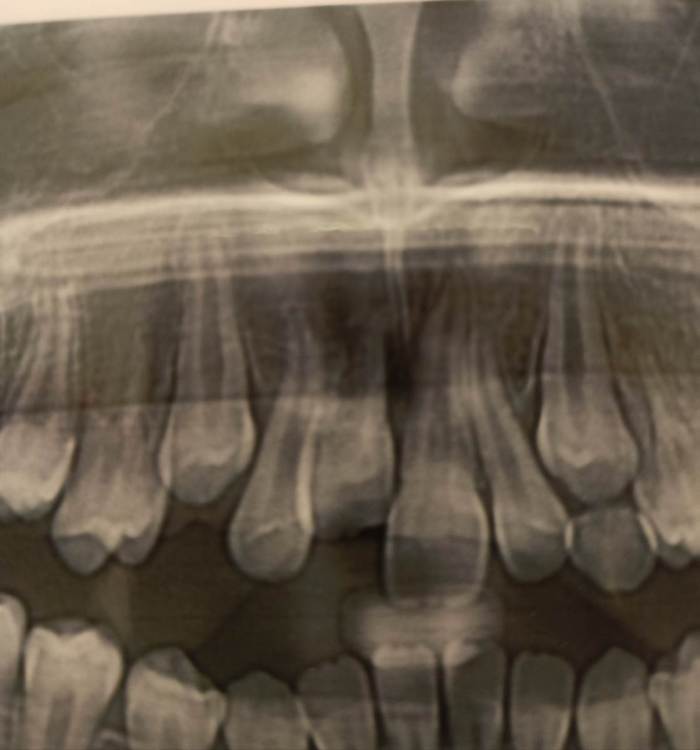

wladdX Опубликовано 4 июля, 2021 Поделиться Опубликовано 4 июля, 2021 Насколько могу судить по приложенным скринам, резорбция корня всё же есть. Судя по Вашему рассказу, проведённая коллегами работа была верной, результат весьма неплохой. Рассчитывать на длительное пребывание зуба 11 в челюсти не приходится. Когда-то его придётся удалить. 1 1 Ссылка на комментарий

Pole4ka Опубликовано 4 июля, 2021 Автор Поделиться Опубликовано 4 июля, 2021 38 минут назад, wladdX сказал: Насколько могу судить по приложенным скринам, резорбция корня всё же есть. Судя по Вашему рассказу, проведённая коллегами работа была верной, результат весьма неплохой. Рассчитывать на длительное пребывание зуба 11 в челюсти не приходится. Когда-то его придётся удалить. Спасибо большое за Ваше мнение и отклик! Нам бы дотянуть до момента, когда можно будет ставить имплант. Честно говоря, особой разницы между прошлогодним снимком (нижним среди снимков) и панорамным не вижу, поэтому возникла надежда, что резорбция приостановлена. А анкелоза нет? Спасибо! @wladdX Спасибо!!! Ссылка на комментарий

wladdX Опубликовано 5 июля, 2021 Поделиться Опубликовано 5 июля, 2021 Резорбция корня + вертикальное расположение = анкилоз. То что зуб был с несформированной верхушкой корня помогло ему простоять так долго после реплантации в растущей челюстной кости. Конечно, хорошо бы, чтоб зуб смог простоять до имплантации, но на мой взгляд это маловероятно. 1 1 Ссылка на комментарий

Pole4ka Опубликовано 6 июля, 2021 Автор Поделиться Опубликовано 6 июля, 2021 @wladdX @wladdX @wladdX 04.07.2021 в 21:44, wladdX сказал: 04.07.2021 в 22:25, Pole4ka сказал: @wladdX 20 часов назад, wladdX сказал: Резорбция корня + вертикальное расположение = анкилоз. То что зуб был с несформированной верхушкой корня помогло ему простоять так долго после реплантации в растущей челюстной кости. Конечно, хорошо бы, чтоб зуб смог простоять до имплантации, но на мой взгляд это маловероятно. Очень жаль, что такой неутешительные прогноз. Нам бы конечно дотянуть до имплантации. Но ведь за год изменений между двумя снимками практически нет, даже внешне (на снимках) стало чуточку лучше. И зуб не изменил цвет и неподвижный. Или это вообще ни о чем не говорит? Спасибо! Вверху 2021 год - панорамный снимок, внизу 2020 - КТ Ссылка на комментарий

Bier Опубликовано 6 июля, 2021 Поделиться Опубликовано 6 июля, 2021 Я вас не порадую: 1. Зуб анкилозирован. 3 часа в физрастворе = нет шансов на реваскуляризацию пульпы и связки. Судя по вашим снимкам однозначно анкилозирование. 2. Что делать теперь и почему: Зуб начал отставать в росте, еще через несколько лет это превратится в нерешаемую эстетическую проблему (вся челюсть будет расти, а зуб и участок челюсти с зубом - нет). Необходимо провести операцию декоронации (спилить коронковую часть зуба глубже уровня костной ткани, удалить то, что осталось от пульпы и дать так зажить. Остатки корня резорбируются сами с замещением на кость. Зато челюсть будет расти вместе с отстальными зубами. восстановить зуб временно на пластике (съемной) потом на брекетах. Имплантация желательно не раньше 21 года. Оставлять так нельзя! Ссылка на комментарий